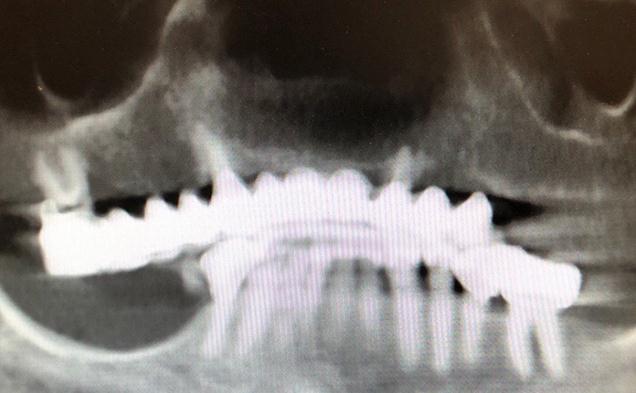

This 46 year old male had non usable loose lower teeth that could not be saved. he did not want to wear a denture during the healing process. I planned to remove all his lower teeth and using guided implant surgery place implant and deliver permanent teeth the same day. The entire case tooth 3 hours and he left the office with a new set of non removable teeth attached to newly placed 7 dental implants. The transformation was remarkable